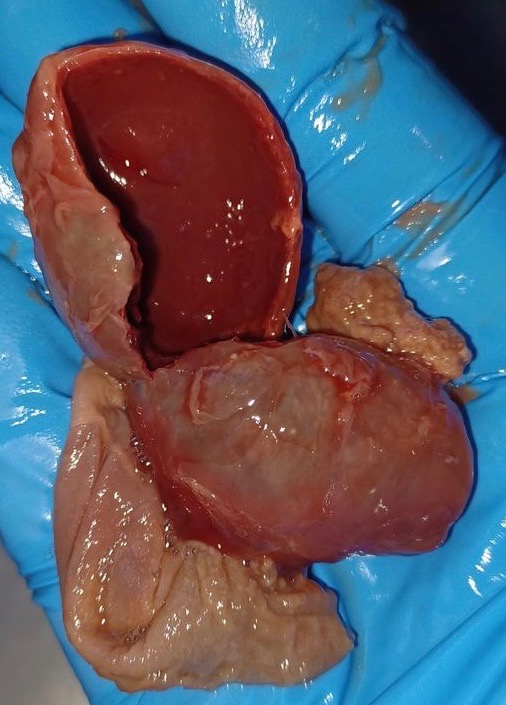

Adenocarcinoma

My two-year-old production red hen had ascites (water belly), which I drained once. She was walking slowly with a waddle, had decreased appetite, thin keel and distended belly. She passed naturally. – Kelli Anderson

Dr Bowes: The hen was very thin and had tumours in her liver and oviduct. She also had a huge recent blood clot as well as evidence of older blood clots. Diagnosis: Adenocarcinoma